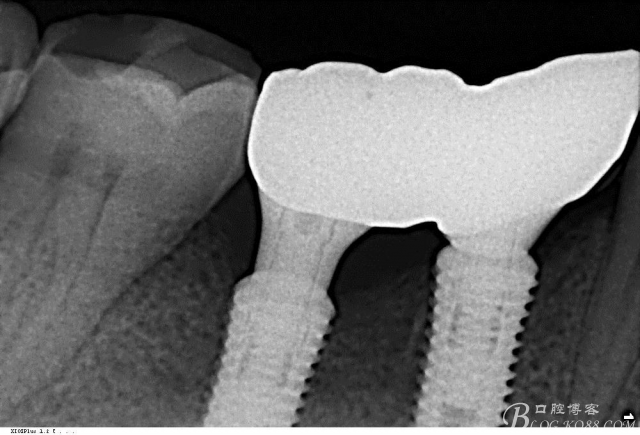

植入植體

C6頰側填入自體骨,嚴密縫合關閉創(chuàng)口

三維檢查種植體位置,方向,平行度